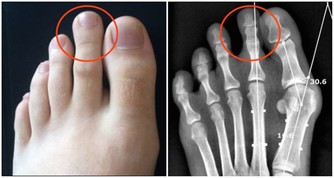

(3)盡量少吃止痛藥

美國食品和藥物管理局(FDA)稱,經常服用布洛芬和萘普生等止痛藥會導致心髒病和中風風險增加10%,建議只在嚴重疼痛時服藥,劑量盡量減小。